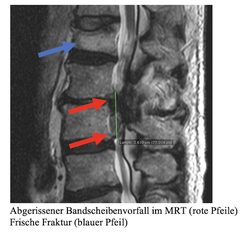

Die Kernspintomographie hat sich als die beste diagnostische Methode für die Wirbelsäule herausgestellt. Mit ihr können kleinste Details der Wirbelsäule dargestellt werden. Sie zeigt zusätzlich Nerven, Rückenmark und Blutgefäße. Die Kernspintomographie hat den Vorteil, dass sie ohne Röntgenstrahlen auskommt. Bei Patienten mit einem Herzschrittmacher kann sie allerdings nicht eingesetzt werden.

Kleine abgerissene und in den Wirbelkanal und das Foramen der Nervenwurzel verrutschte Bandscheibenfragmente können CT gesteuert erfolgreich mit speziellen kleinsten Endoskopen abgetragen werden..